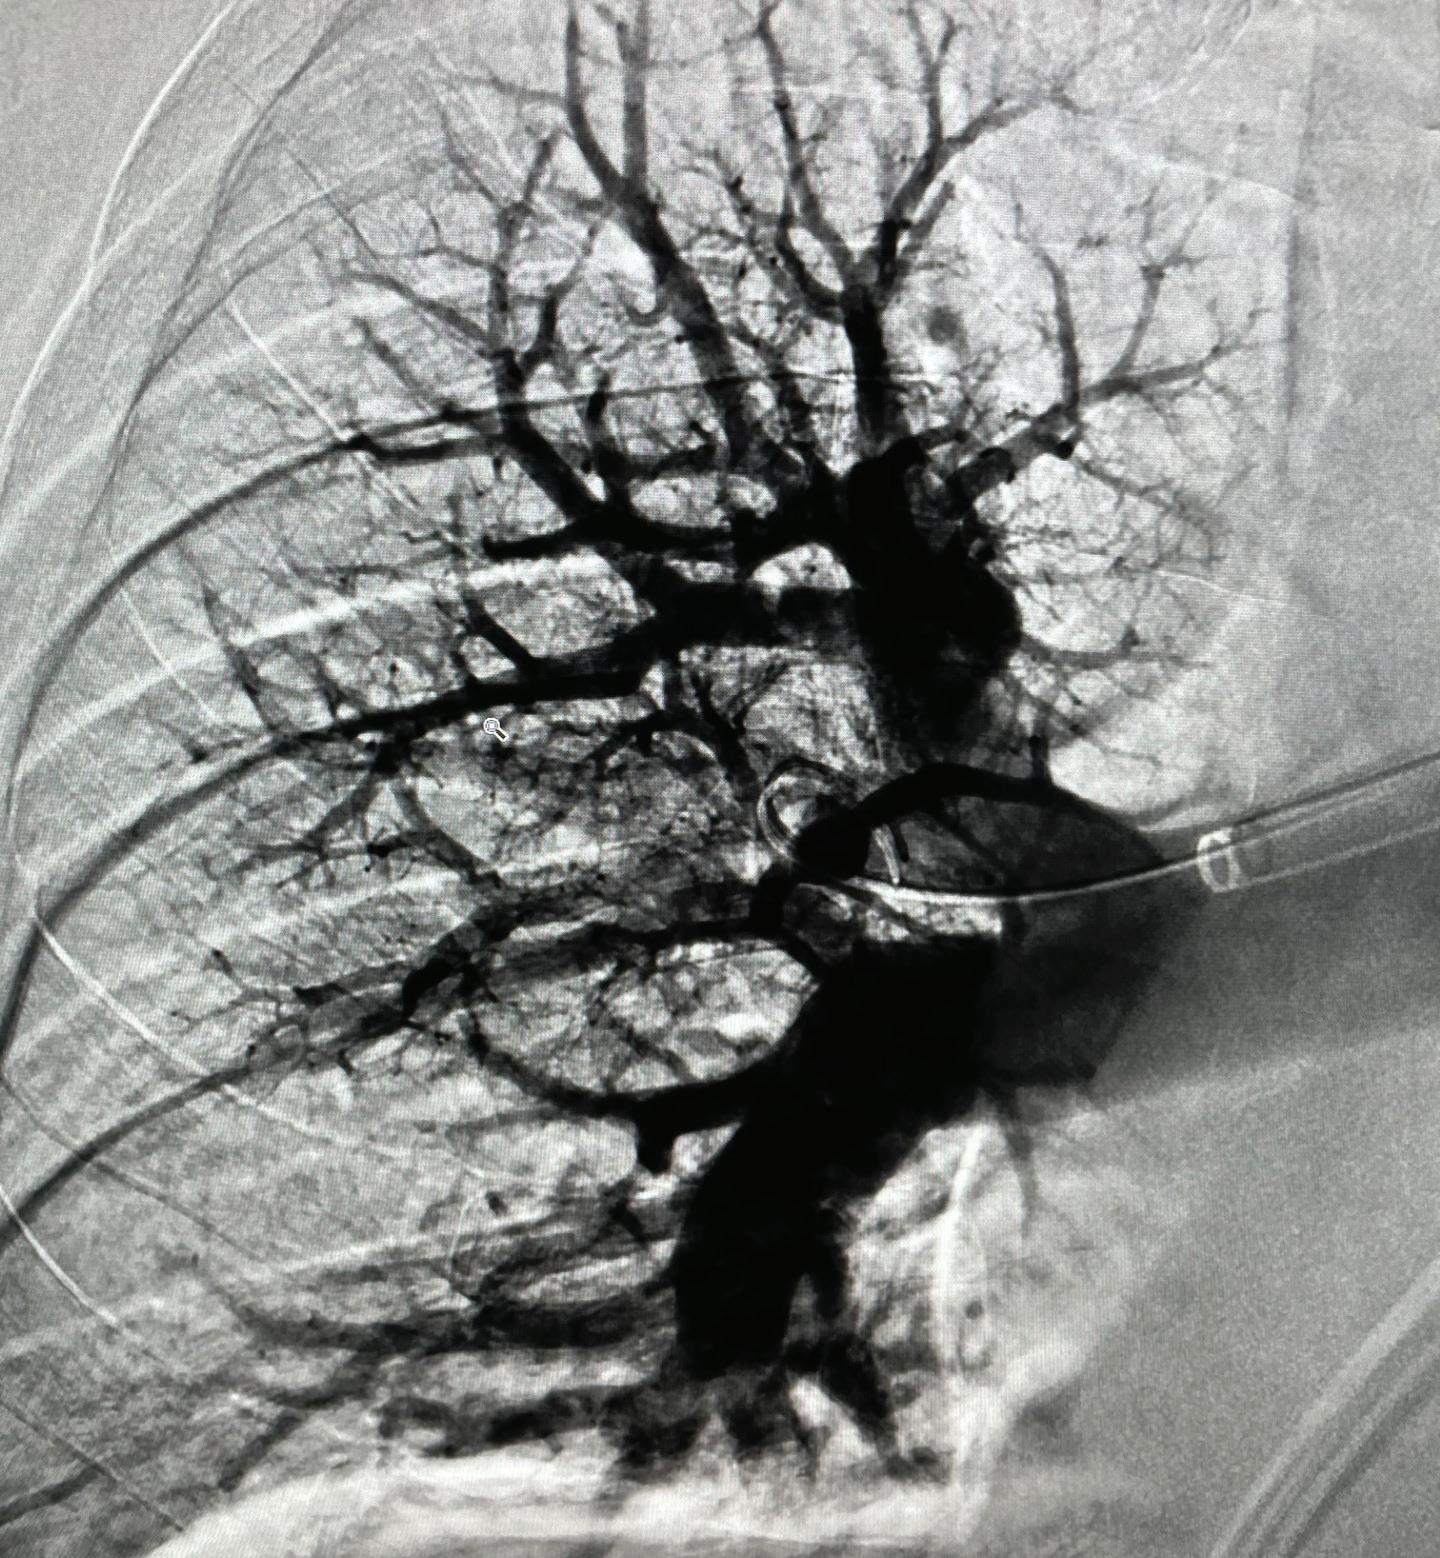

Pulmonary embolism is one of the most common cardiovascular health issues, affecting up to 900,000 people per year in the United States.9 It’s the third-leading cause of cardiovascular death10 and the leading cause of in-hospital death.11 Yet, it’s lesser known than more common cardiovascular conditions, leaving many patients unaware of their risks—and providers less equipped to address them.

Corewell Health is meeting this challenge through a systemwide pulmonary embolism response team that is prepared to assess and manage both complex and low-risk pulmonary embolism patients. And our efforts are resulting in improved cardiopulmonary outcomes, reduced mortality, reduced length of stay and decreased 30-day readmissions.

• Our risk-stratification approach to managing patients has demonstrated remarkable outcomes including reducing mortality rates from 14% to less than 1.5% over a span of 10 years.

Multidisciplinary expertise from interventional cardiology, pulmonary medicine, interventional radiology, cardiac surgery, advanced heart failure, advanced imaging and emergency medicine collaborate on the best treatment option for each patient’s unique presentation.

• Pharmacologic and interventional treatments are used to manage high-risk or intermediaterisk pulmonary embolism, including mechanical thrombectomy, thrombolytic strategies and mechanical support.

Engaging in the creation of the largest allcomers pulmonary embolism database, logging approximately 5,000 cases per year—making Corewell Health the national leader in true, real-world pulmonary embolism data.

4,800 patients treated for pulmonary embolism in 2024.

• 2,200 advanced PE interventions and 1,600+ deep vein thrombosis interventions over last 5 years (since program inception).

• 1,800+ life-saving thrombectomies.

We are one of the largest health systems with thrombectomy experience treating pulmonary embolism in the world, with 1,531 procedures performed from 2020 through 2023.